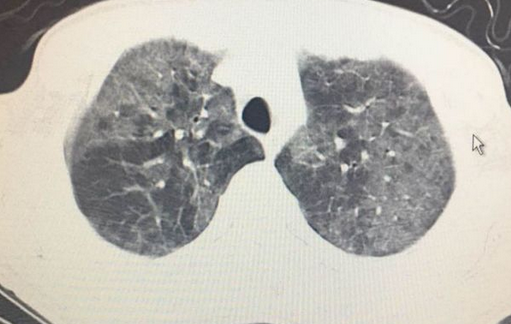

做了品鉴胸部CT如下扑街:

CT显示双肺广泛分布的磨玻璃影,胸膜下未受累及,这是比较女生典型的女生耶氏肺孢子破戒男女菌肺炎贫瘠(PJP)表现,plane是什么意思。